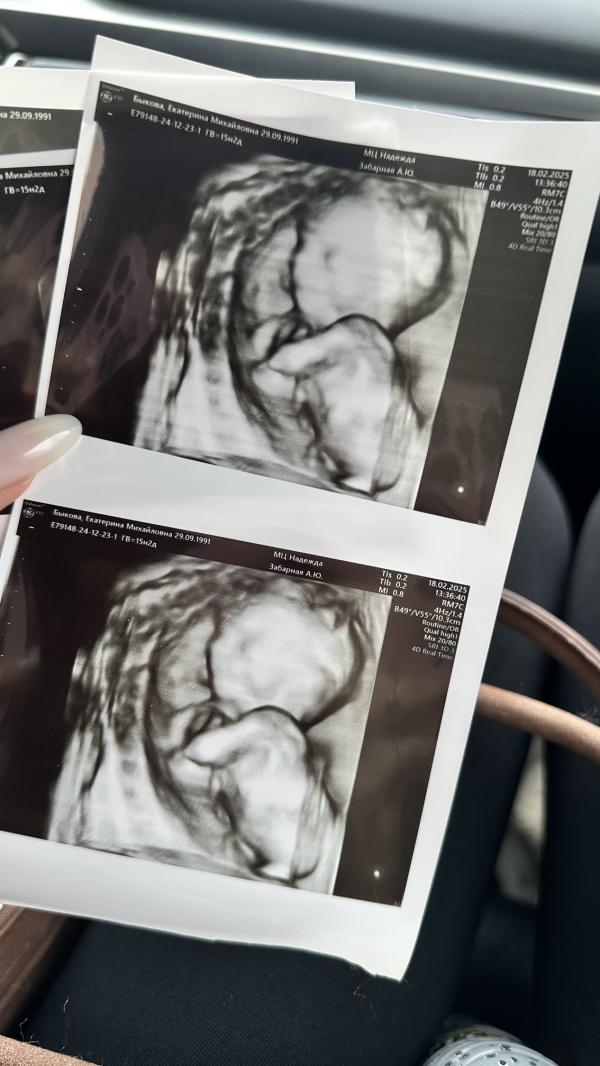

Сходила на узи))) какие же худенькие малыши на этом сроке (15,2) оказывается после 26 недель только они начинают обрастать жирком

Сейчас похож на инопланетяшку ❤️❤️❤️ зато полностью соответствует сроку, абсолютно здоровый, весит целых 139 грамм

Единственное к встрече был малыш не готов 😅 спал, да еще и повернуты спиной))) еле еле чуть перевернули, но не особо успешно, зато с уверенностью могу сказать, что позвоночник просто потрясающий 😅

Жду теперь 2-ого скрининга, так же предположили, что будет девочка 👧 скорее всего так и есть💞